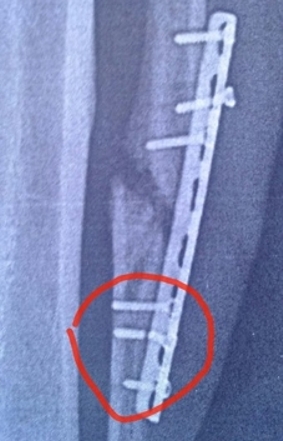

У Айрата Тагирова сломался шуруп в ноге

Владелец SunDale beach Club Айрат Тагиров сообщил в своем микроблоге о сломавшемся шурупе в креплении кости ноги:

"Я - Плющенко! Шуруп сломался в ноге! Через неделю опять оперировать!".